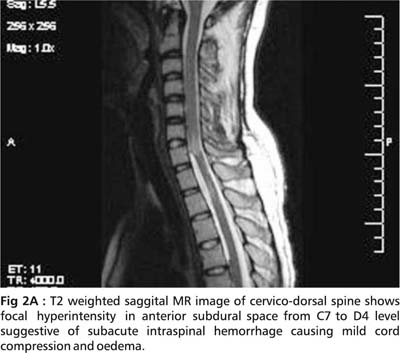

An initial MRI cervical spine revealed cervical cord edema at C5 to C7 ( Fig.1). A repeat MRI done after 15 days showed striking changes in the same area (Fig. 2A, 2B, 2C and 2D).

The cervical MR findings are suggestive of subacute spinal subdural hemorrhage appearing hyperintense on both T1 and T2 images. Serpigenous flow voids were seen on axial sections suggestive of Arterio-Venous malformation (AVM). Unfortunately, a subsequent angiographic study could not be done.